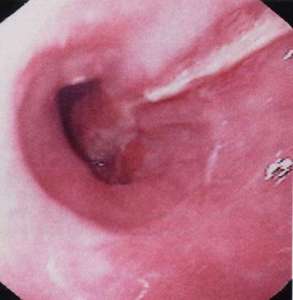

Для уточнения диагноза врач должен обследовать пищевод и желудок пациента изнутри. Для этого он использует эндоскоп. Для осмотра желудка применяется специальный эндоскоп (гастроскоп). В некоторых случаях исследуются соответствующие артерии. Применяя эти методы исследования, врач убеждается в правильности постановки диагноза и только после этого назначает необходимое лечение.

Если нижняя треть пищевода раздражена или как-то иначе повреждена, то при рвоте, отрыжке или сильной икоте у пациента могут появиться небольшие надрывы слизистой оболочки. При разрыве слизистой оболочки из пищеварительного тракта начинается артериальное кровотечение, в результате которого жизни пациента может угрожать серьезная опасность.